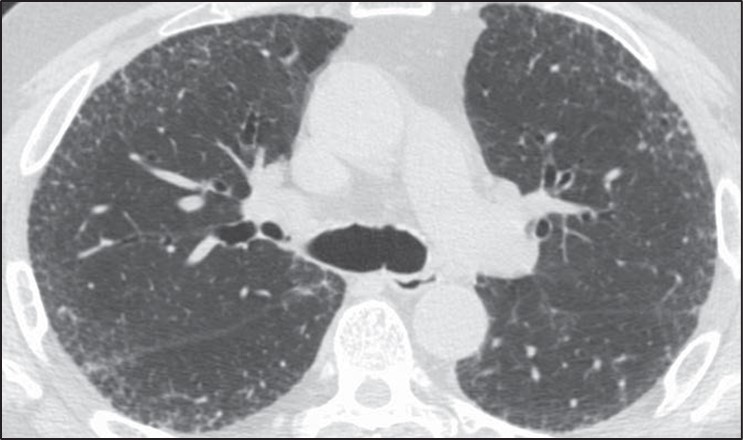

Formulating a differential diagnosis of diffuse nodular lung disease is done by identifying the distribution of nodules in relation to the pulmonary lobular anatomy. Three distributions have been described: perilymphatic, random, and centrilobular [23–25]. The perilymphatic distribution is characterized by patchy, clustered nodules that are concentrated most frequently in the peribronchovascular and subpleural interstitium. Random nodules will also be seen in the subpleural lung; however, they are not clustered but instead show diffuse homogeneous lung involvement. Centrilobular nodules are characterized by a distinct lack of nodules involving the subpleural interstitium.

The determination of the predominant pattern of diffuse nodular lung disease has several pitfalls. The perilymphatic pattern shows significant heterogeneity in the distribution of nodules. Although peribronchovascular and subpleural nodules are most typical, nodules in the interlobular septa, which also contain lymphatics, may predominate [26]. These cases may be confused for lymphangitic spread of tumor or pulmonary edema, although the thickening of the interlobular septa in pulmonary edema should be smooth, not nodular. The centrilobular interstitium is continuous with the peribronchovascular interstitium. Rarely, lymphatic diseases may have a predominance of centrilobular nodules overlapping with the centrilobular distribution (Fig. 10).

Fig. 10—Axial high-resolution CT scan shows centrilobular nodules in perilymphatic disease. Many centrilobular nodules (arrows) are present in this patient with sarcoidosis. Subpleural nodules reflect perilymphatic distribution of disease.

Although many centrilobular nodules may be present in lymphatic diseases, nodules should also be seen in the peribronchovascular or sub- pleural interstitium. This is in distinction to the centrilobular pattern in which only centrilobular nodules are present and no subpleural nodules should be seen. Lastly, diseases typically associated with a perilymphatic distribution of nodules (such as sarcoidosis) may occasionally show a fairly homogeneous involvement of the lung, mimicking a random distribution [27] (Fig. 11).